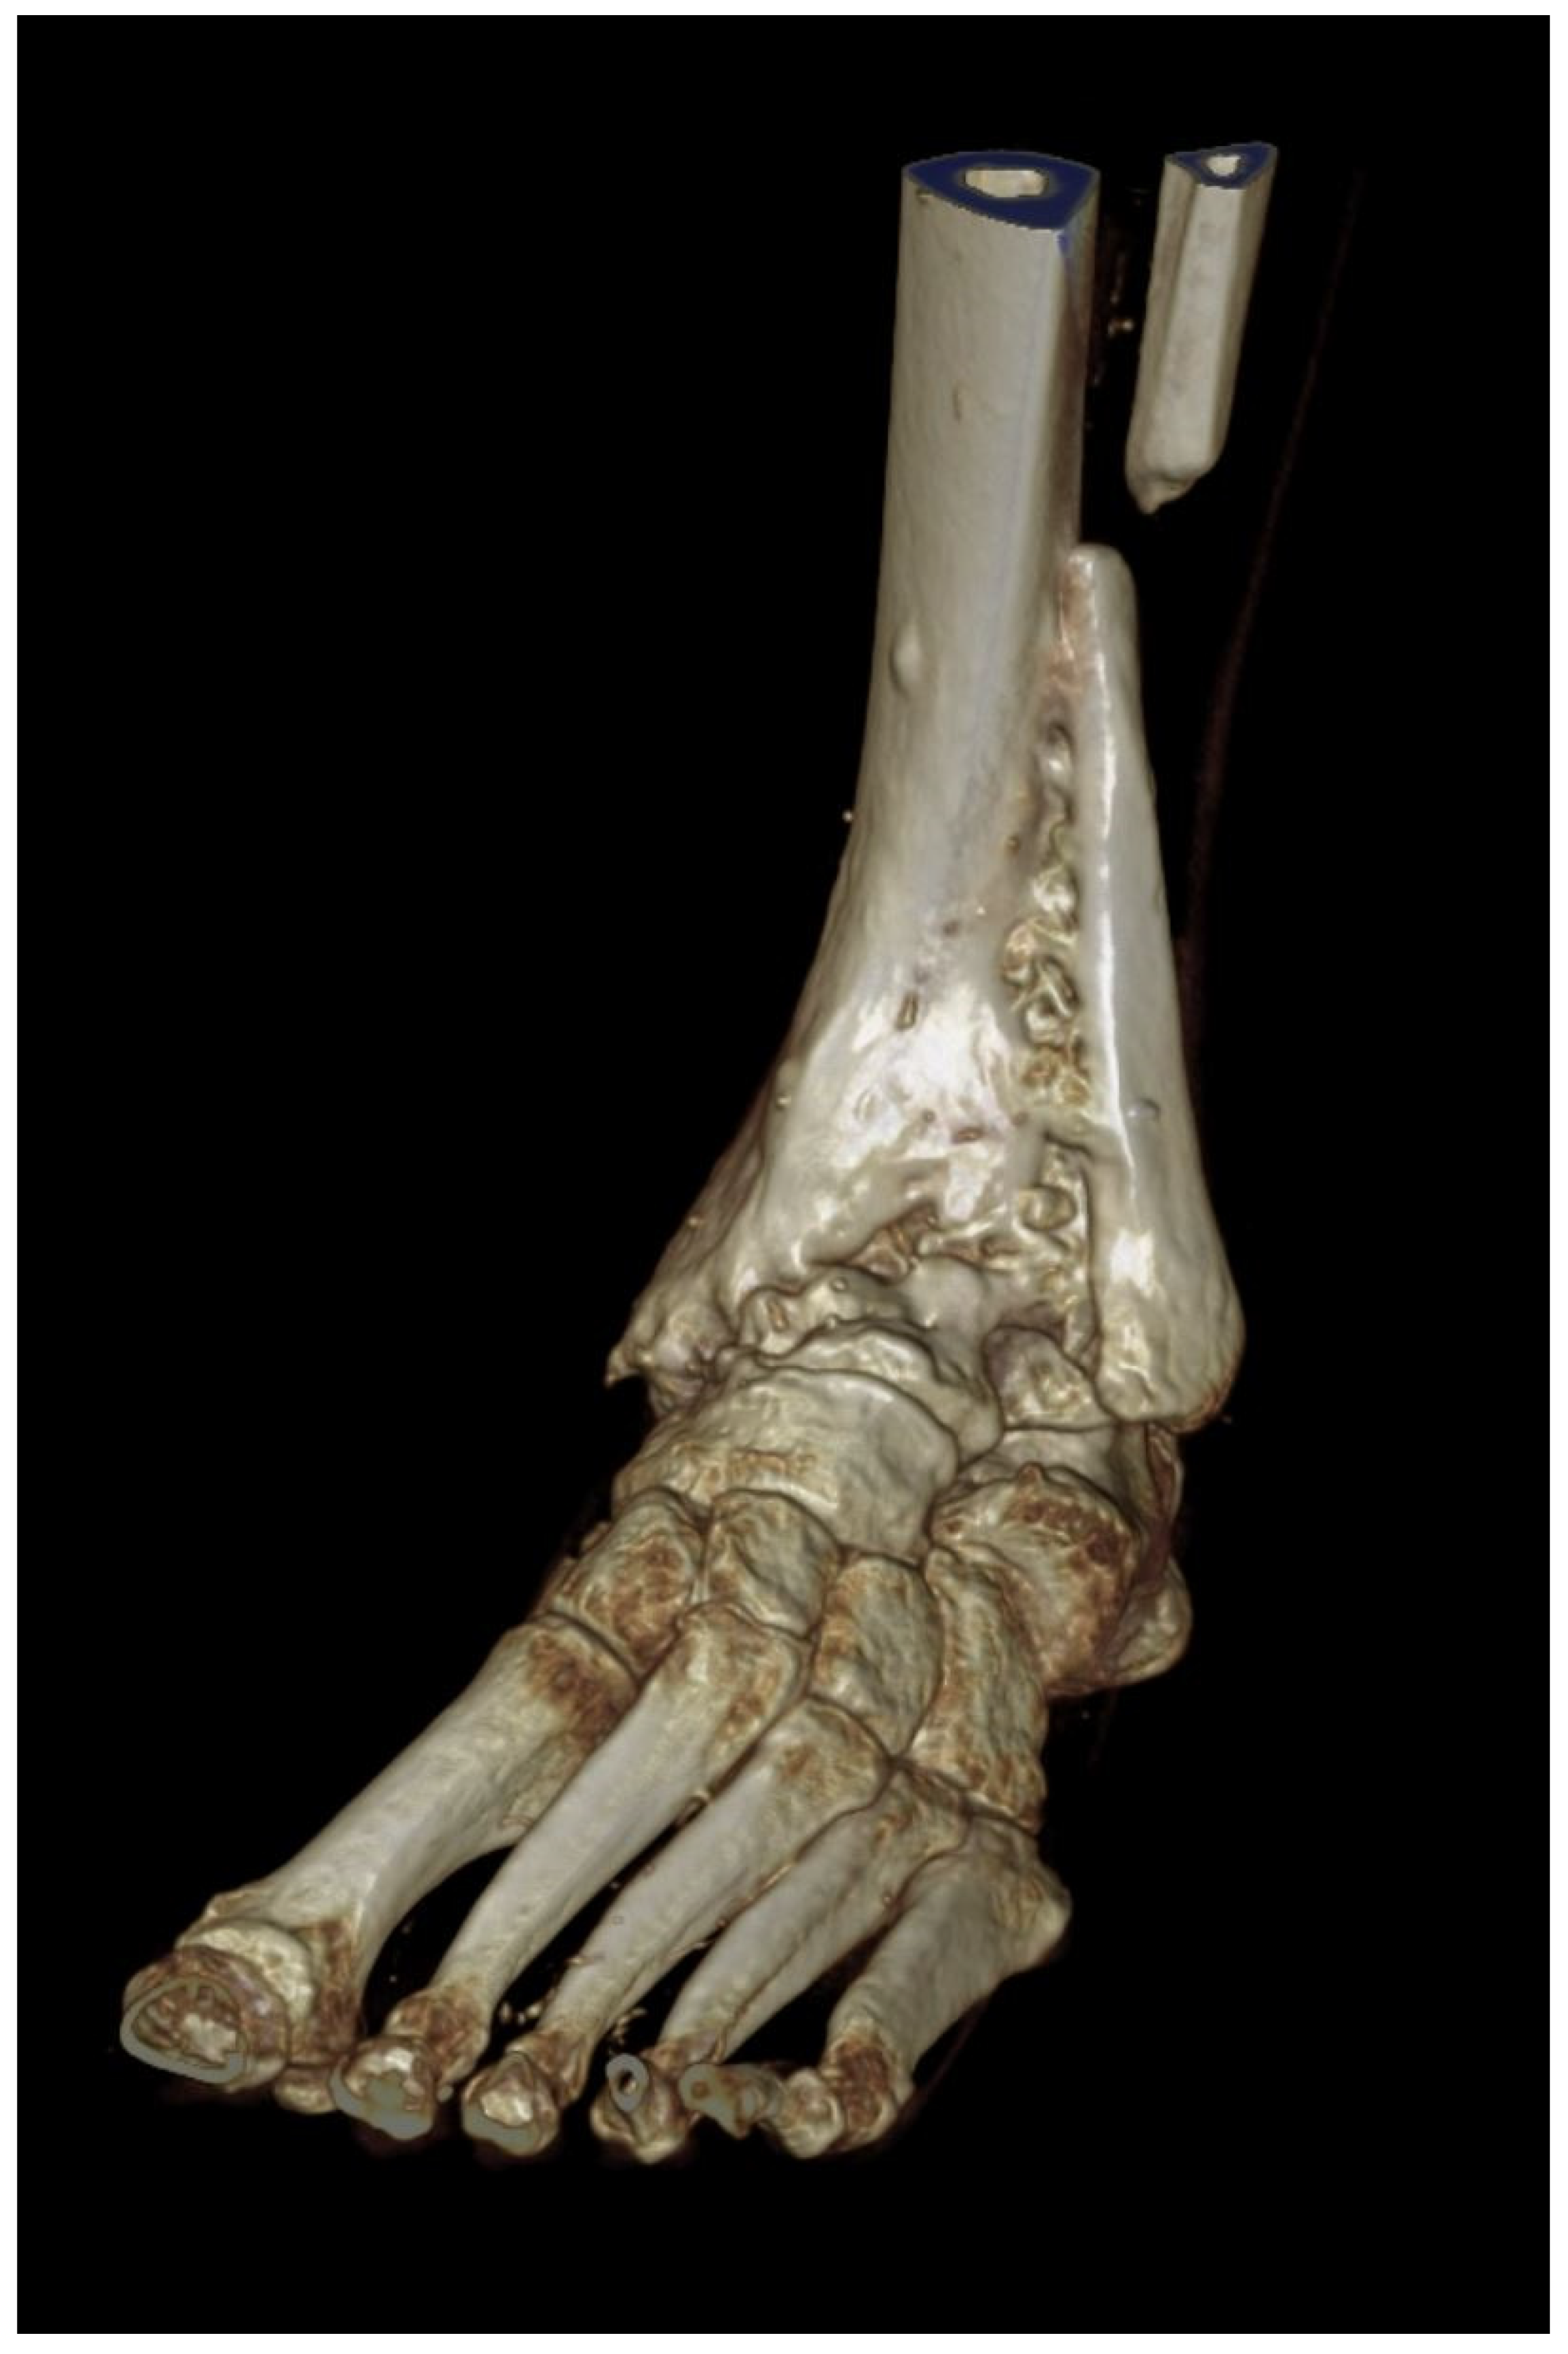

Arthrodesis and Defect Bridging of the Upper Ankle Joint with Allograft Bone Chips and Allograft Cortical Bone Screws (Shark Screw®) after Removal of the Salto-Prosthesis in a Multimorbidity Patient: A Case Report

2. Case Presentation